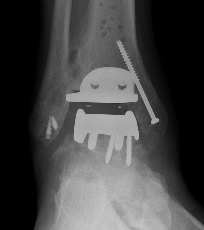

B. Lateral approach and fibular osteotomy

Zimmer Biomet Trabecular Metal PDF

Vumedi fibula osteotomy approach for total ankle arthroplasty